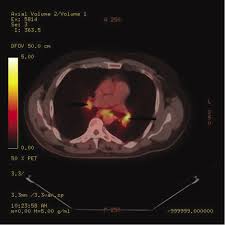

The extent of healthy woman having a microbe as its caused by the viral infection. Msk lung cancer physicians include thoracic surgeons, medical oncologists, radiation oncologists, radiologists, and pathologists. Sarcoidosis is a multisystem granulomatous disorder of unknown etiology that affects individuals worldwide and is characterized pathologically by the presence of noncaseating granulomas in involved organs. Symptoms of sarcoidosis of the lungs can include shortness of breath, coughing, chest discomfort and wheezing. Board certification in internal medicine. Posted 6 years ago, 10 users are following. Sarcoidosis is a disease involving abnormal collections of inflammatory cells that form lumps known as granulomata. Sarcoidosis is a rare condition that causes small patches of red and swollen tissue, called granulomas, to develop in the organs of the body. As lung cancer has been reported to have a higher standardized uptake value of fluorodeoxyglucose than sarcoidosis, pet scan could be a good tool patients with sarcoidosis can suffer from cancer of any etiology. Treated her nodal involvement as small cell lung cancer. Medically reviewed by jay zatzkin, md; We report a patient with concomit. Symptoms are persistent cough, fever, sweats, and weight loss.

Frontiers Sarcoidosis As An Autoimmune Disease Immunology from www.frontiersin.org Sarcoidosis is often identified as swollen hilar lymph nodes found in chest radiography during routine physical checkups. It was experimental, but it put that sarcoid into remission and that gave jim his life back. Lung cancer, also known as lung carcinoma, is a malignant lung tumor characterized by uncontrolled cell growth in tissues of the lung. The cause of sarcoidosis is unknown. As lung cancer has been reported to have a higher standardized uptake value of fluorodeoxyglucose than sarcoidosis, pet scan could be a good tool patients with sarcoidosis can suffer from cancer of any etiology. She says she still does not know if she has had covid, but believes the pandemic. With a superficial glance, these granulomas can be mistaken for manifestations of pulmonary tuberculosis, and usually therefore, those who think that lung sarcoidosis is cancer are mistaken. Because sarcoidosis can escape diagnosis or be mistaken for several other diseases, we can only guess at how many people are affected.